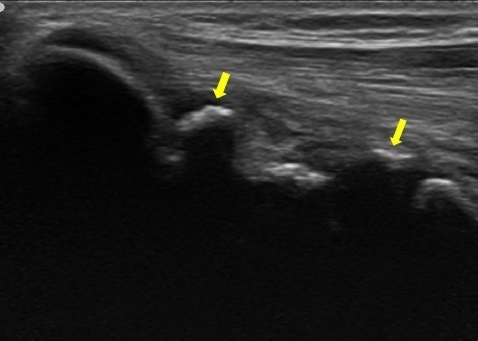

超音波観察では正常肘ではみられないような骨の不正像(↓)が認められました。

正常の肘のエコー画像

内側型野球肘のエコー画像